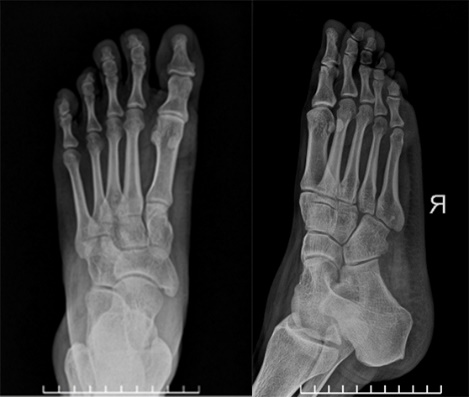

Ảnh chụp xương bàn chân của một người bệnh như hình bên. Trong kỹ thuật chụp ảnh này,

Ảnh chụp xương bàn chân của một người bệnh như hình bên. Trong kỹ thuật chụp ảnh này, loại tia nào đã được sử dụng?

Trong y học, tia X được ứng dụng để chụp, chiếu.